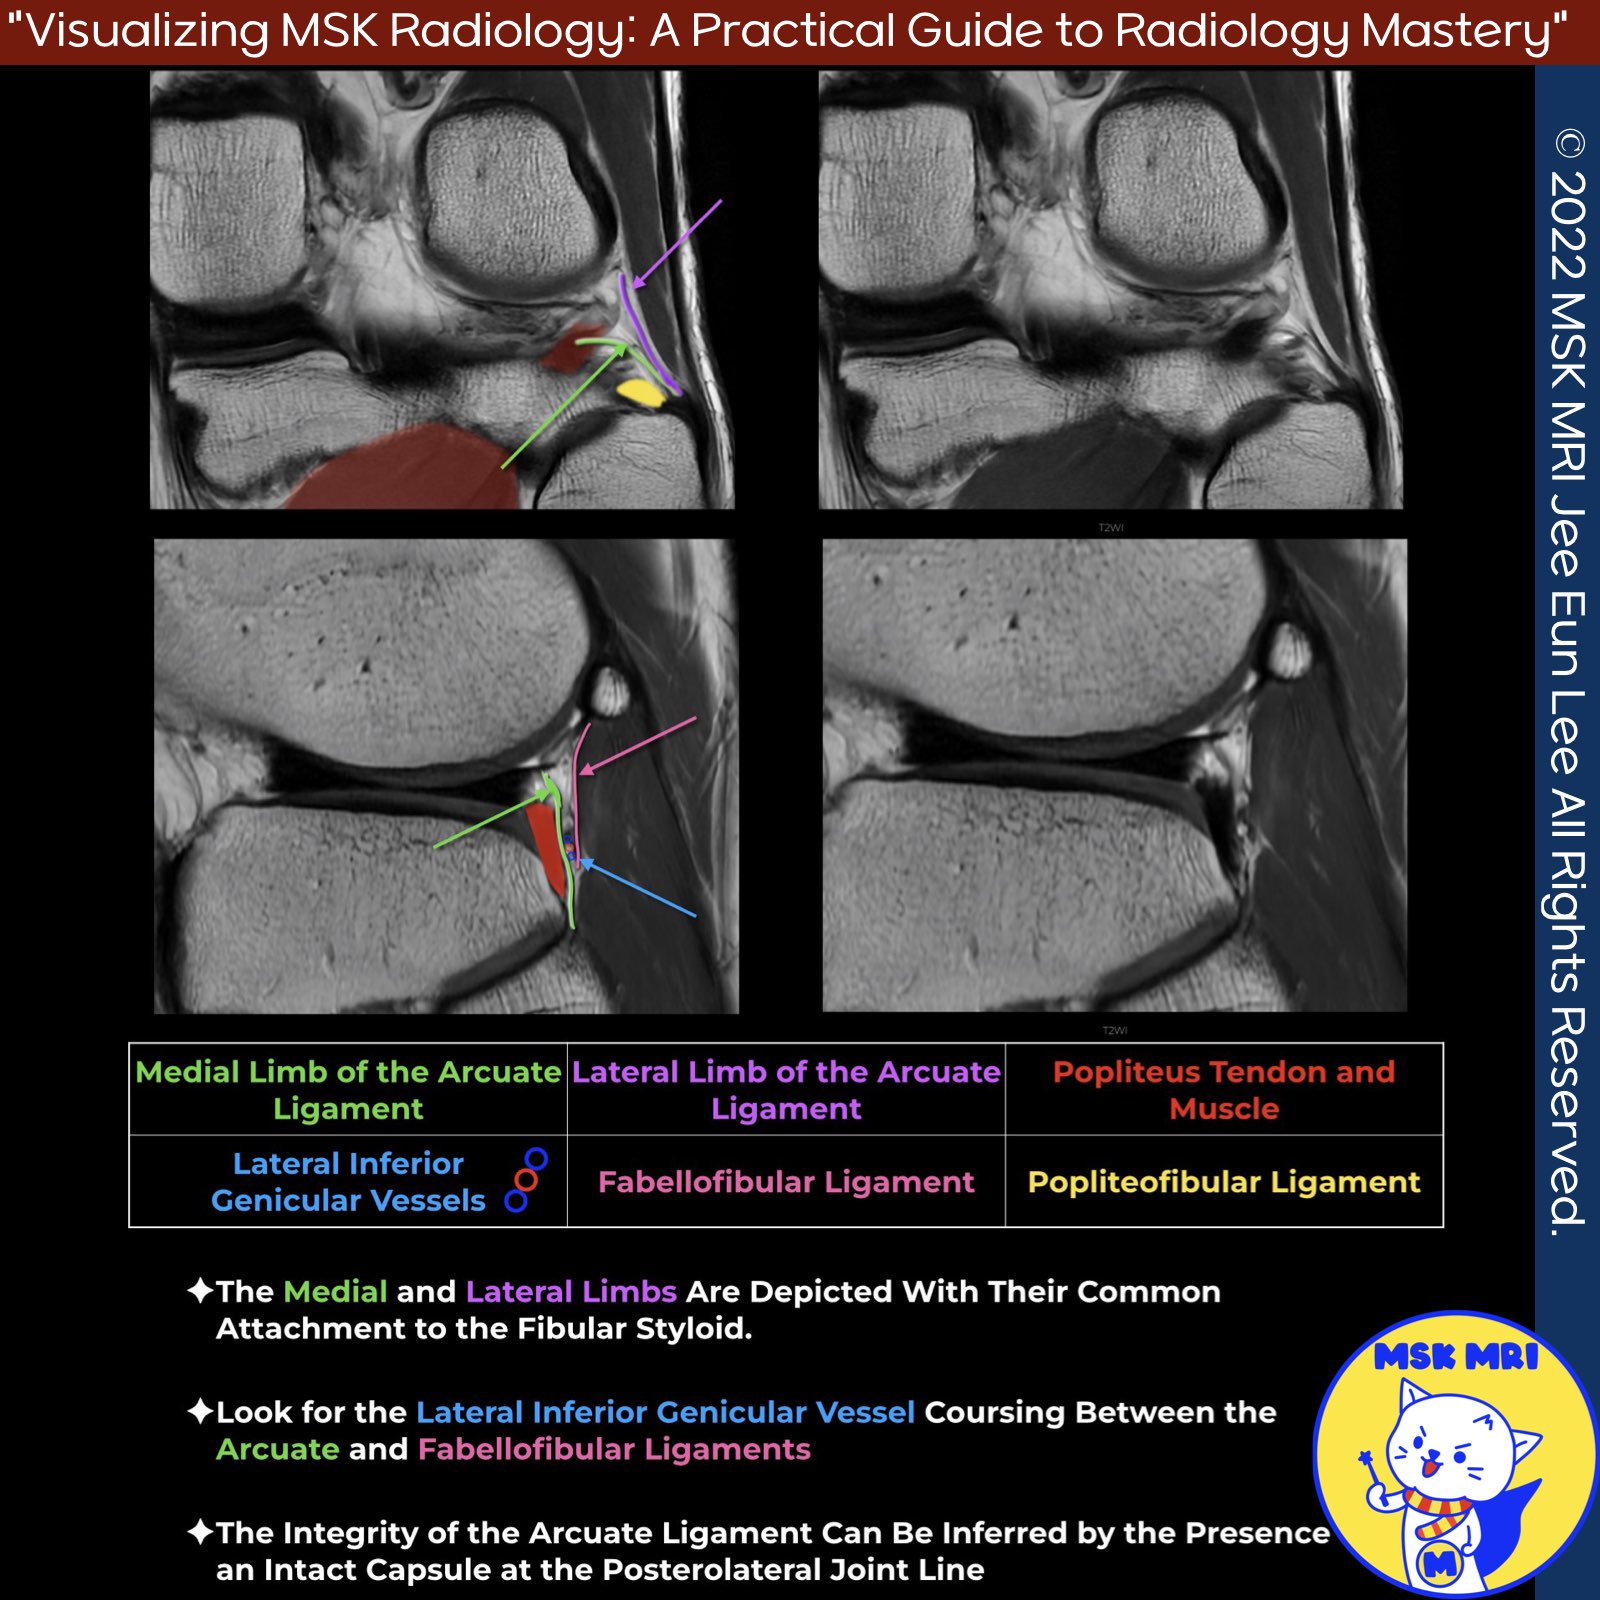

📌 Anatomy of the Arcuate Ligament

- Y-shaped thickening of the posterolateral capsule

- Runs to apex of fibular styloid process

- Lateral limb attaches to lateral femoral condyle and posterolateral joint capsule

- Medial limb attaches to posterior knee capsule and oblique popliteal ligament

✅ Variability and Visualization

- Variably present structure

- Difficult to visualize directly on MRI even when present

✅ Key Point 1: No Need to Decipher Exact Anatomy

- Injury can be inferred from increased pericapsular signal around posterolateral capsule

- Torn medial limb seen posterior to popliteus tendon

- Integrity inferred from intact posterolateral joint line capsule

✅ Key Point 2: Sagittal Anatomy to Remember

- Popliteus tendon lies deepest, easy to identify

- Lateral inferior genicular vessel also easily seen

- Medial limb between popliteus and genicular vessel

- Fabellofibular ligament superficial to genicular vessel, connects to fabella

- If fabellofibular ligament prominent, lateral limb may be small/absent